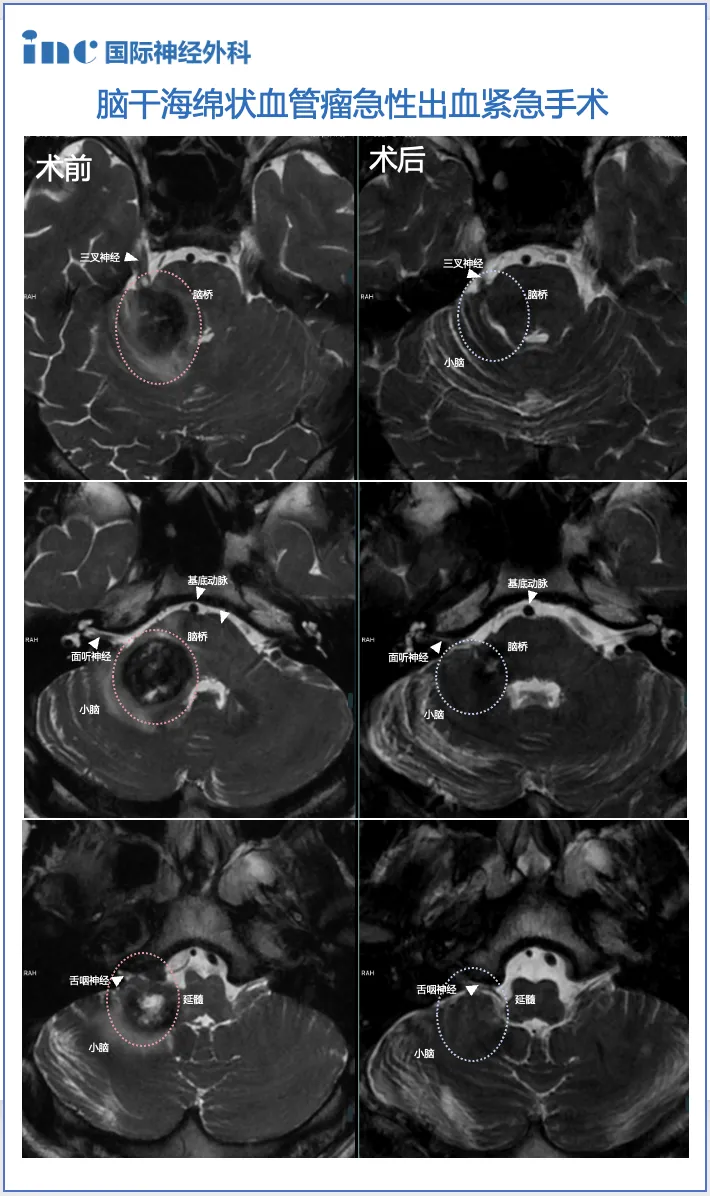

患者荣荣初期表现为间歇性头晕症状,随后出现右侧耳鸣、右侧面部麻木及舌部感觉异常等神经系统症状。当地医院影像学检查发现脑干及右侧桥臂区域存在异常信号,高度怀疑海绵状血管瘤可能。进一步检查发现小脑内复杂静脉畸形,伴较大引流静脉穿过脑桥中线区域。

脑干手术风险极高,该区域解剖结构复杂,掌管重要生理功能。海绵状血管瘤切除手术需在保留神经传导束完整性的前提下完整切除病灶,防止再出血。患者血管瘤体积较大,合并复杂静脉畸形,引流静脉穿过脑桥中线更增加手术难度。

手术顺利完成,术后患者转入ICU监护,未出现新的神经功能损伤。术后第三天患者即可下床活动,头晕症状显著缓解。术前存在的严重眩晕在术后第二天基本消失,患者临床症状得到明显改善。

术后三个月影像学复查显示,右侧脑桥及小脑臂内海绵状血管瘤完全切除。患者神经功能恢复超出预期,生活质量显著提高。现代神经外科技术包括术中神经导航和神经电生理监测的应用,显著提升了脑干病变手术的安全性和精准度。